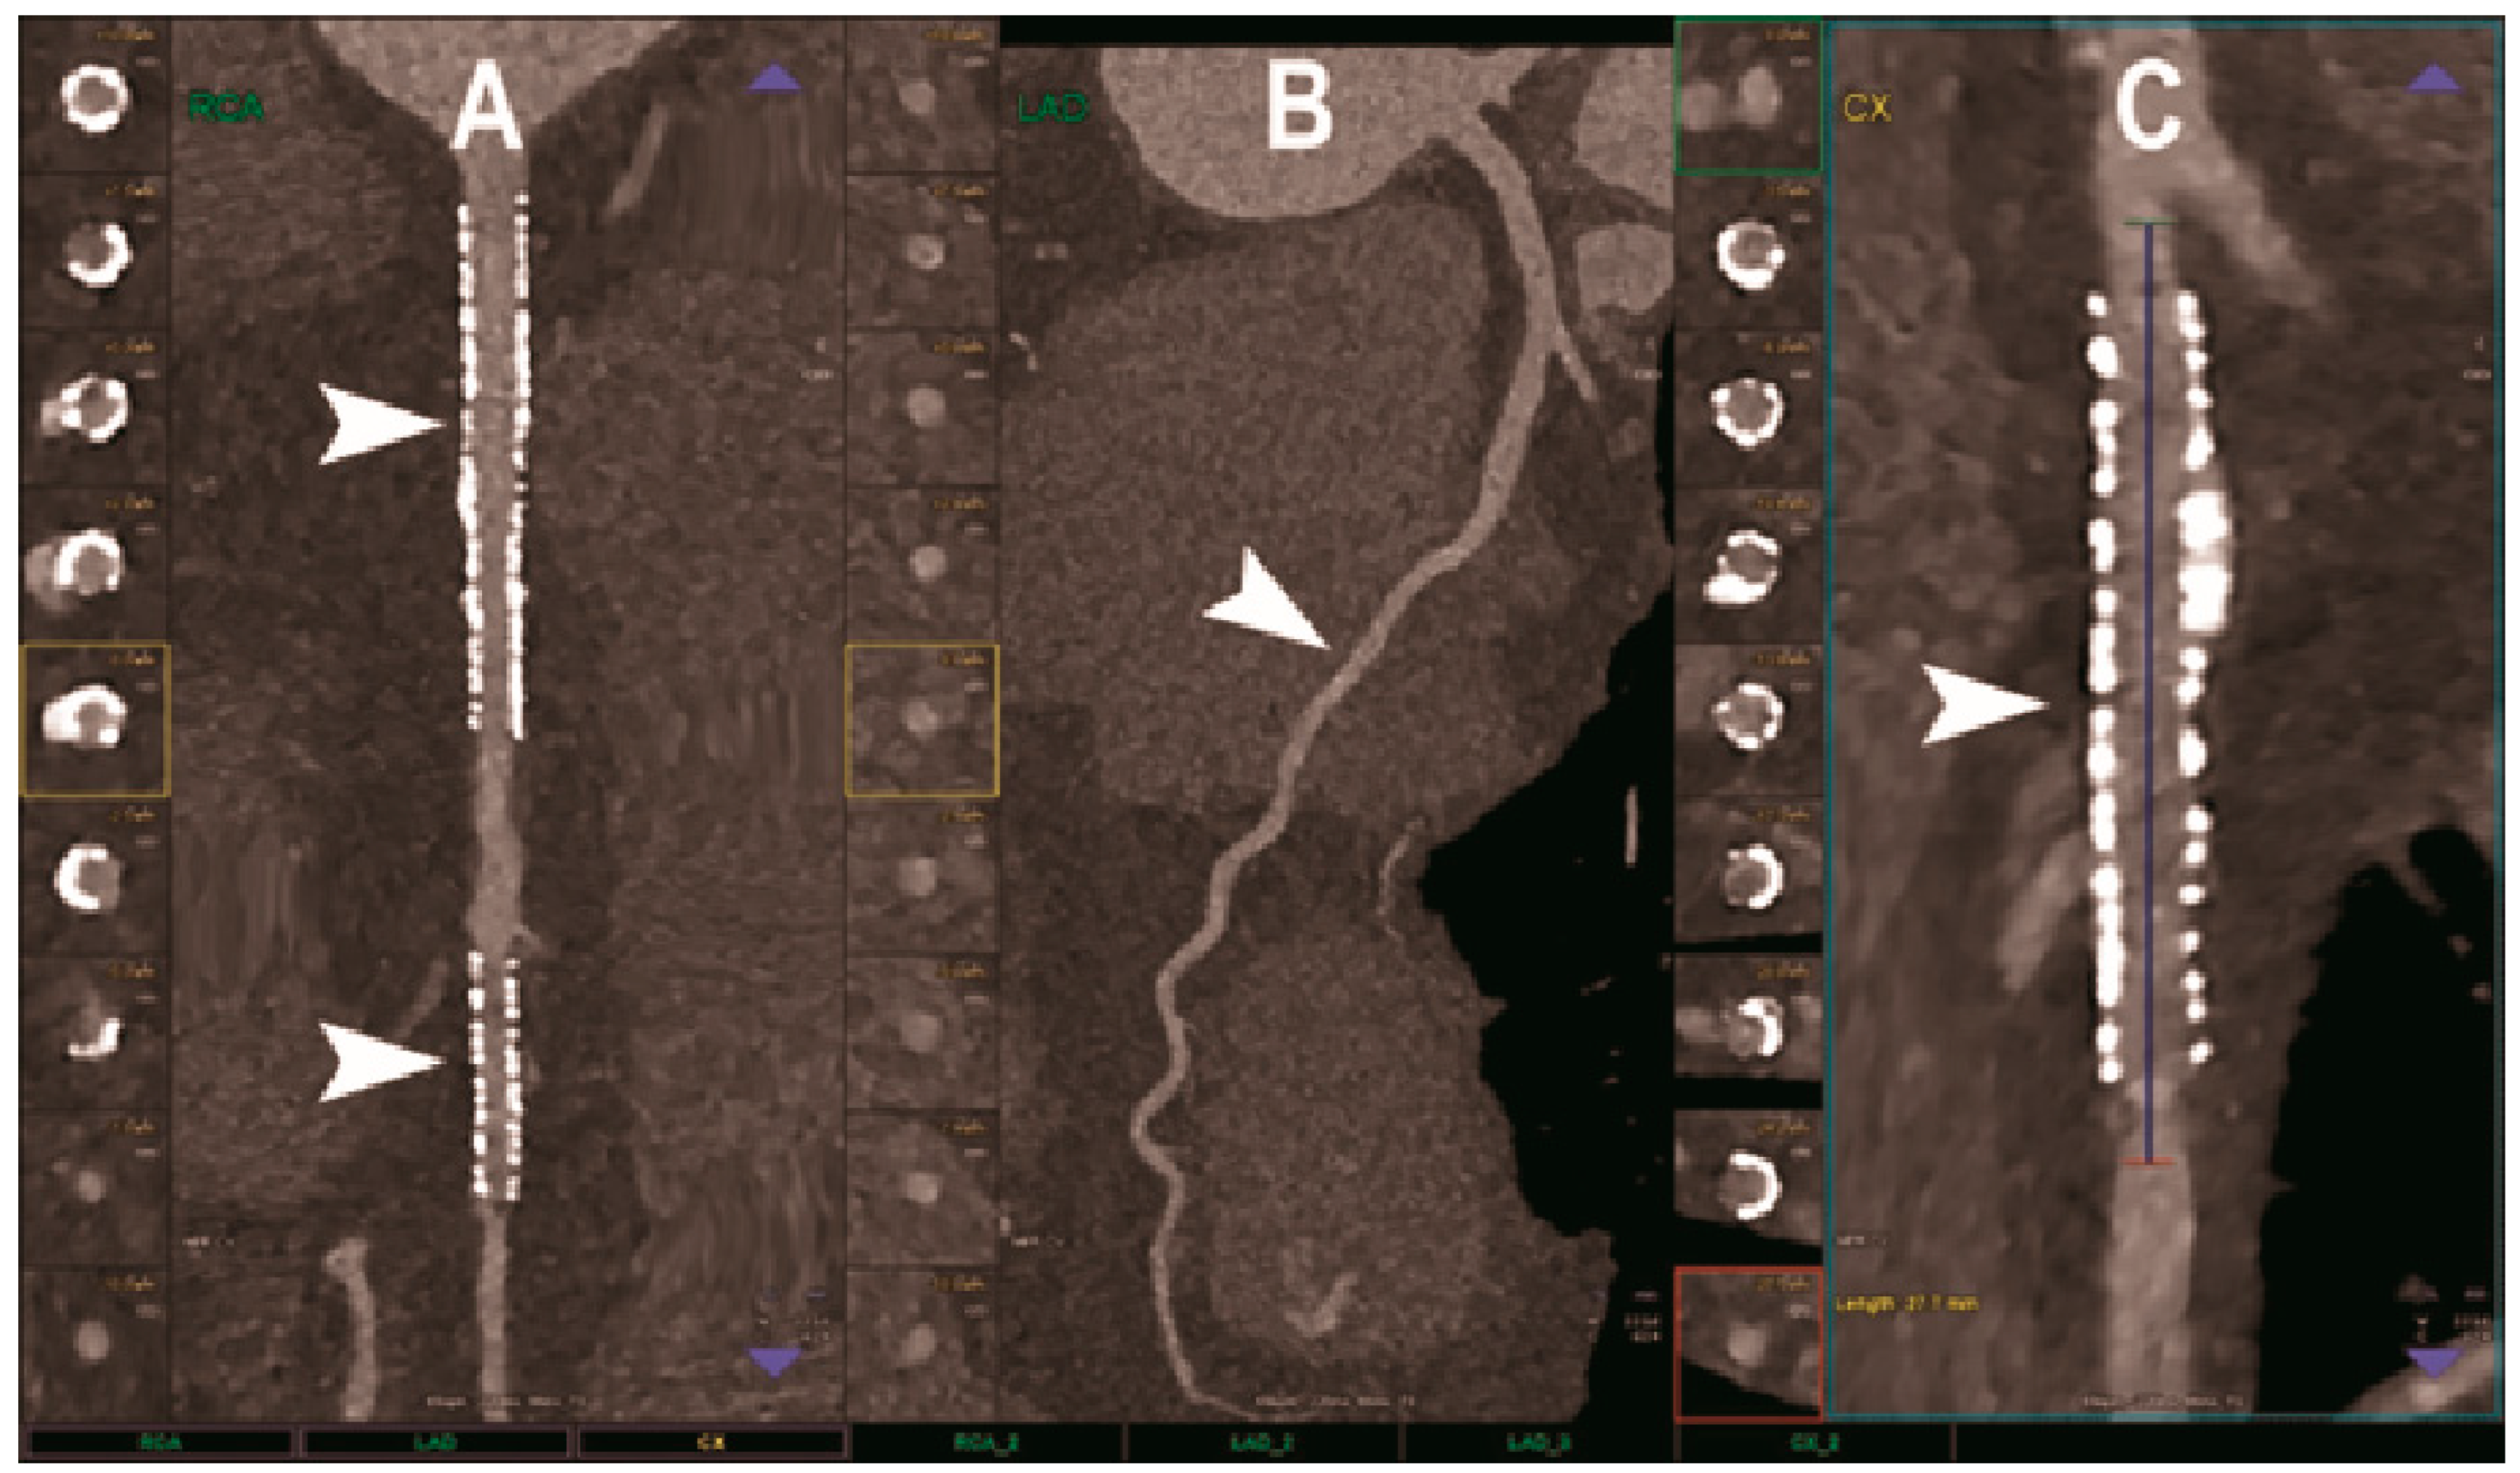

Figure 2.

Cardiac CT using photon-counting computed tomography. The figure shows advanced multiplanar reconstructions of a coronary tree derived from a Photon-Counting CT (Scanner: NAEOTOM Alpha, Siemens) acquisition (A–C). In (A) we can see the right coronary artery with 2 stents (arrowheads), one proximal and one distal (much smaller), without any issue in the intrastent visualization of the arterial lumen. In (B), the left anterior descending coronary artery is depicted along its entire course (down to and beyond the left ventricular apex) with great detail and an evident deep intramyocardial course in the middle segment of the vessel (arrowhead). In (C), the left circumflex coronary artery also shows a stent with perfect intrastent visualization and patency (arrowhead).

The largest published clinical study of PCCT for CAD, involving 92 patients, demonstrated excellent imaging quality, a very high CNR, and a good ability to assess coronary segments and vessels, even in cases of calcified plaques and stents [72]. Indeed, only 5% of the segments were rated non-diagnostic. The radiation dose was generally low and depended strongly on the scan mode. Nine patients also underwent invasive coronary angiography as reference standard and the PCCT showed very high diagnostic performance for significant CAD on a per segment level (sensitivity 92% and specificity 96%).